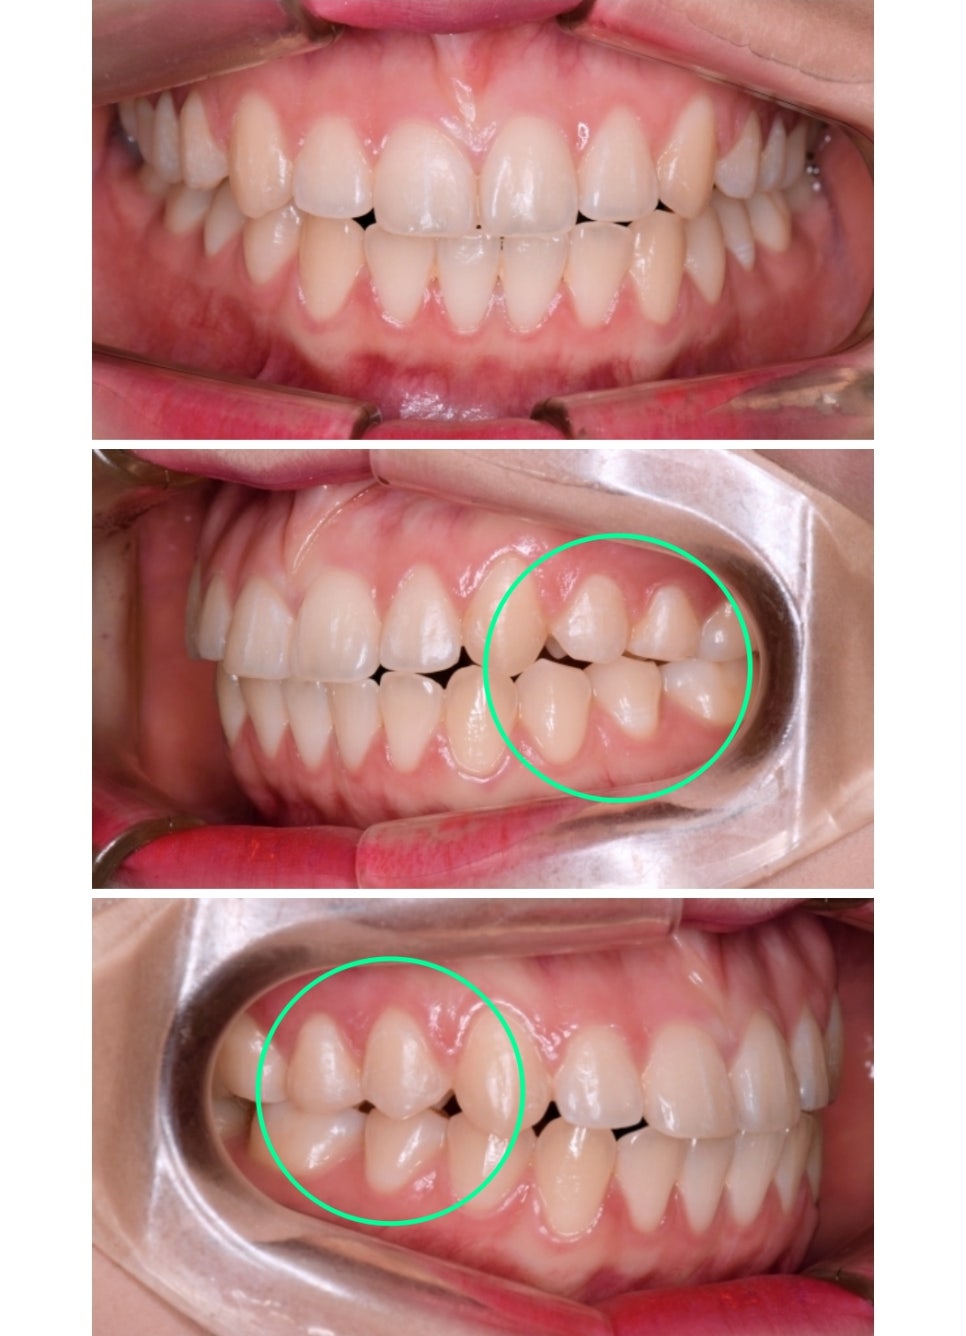

돌출입과 비뚤배뚤한 치열을 해결하는 것 보다 중요한 부분은 쉽게 눈에 띄지않는 어금니의 교합입니다.

육안으로 보여지는 배열만을 맞추는것은 당장은 큰 문제가 없을지 몰라도 시간이 지나면서 치아건강이 악화 될 수 있습니다.

촬영일자 : 19.07.02 / 본 이미지는 보정이 들어가지 않은 이미지입니다.